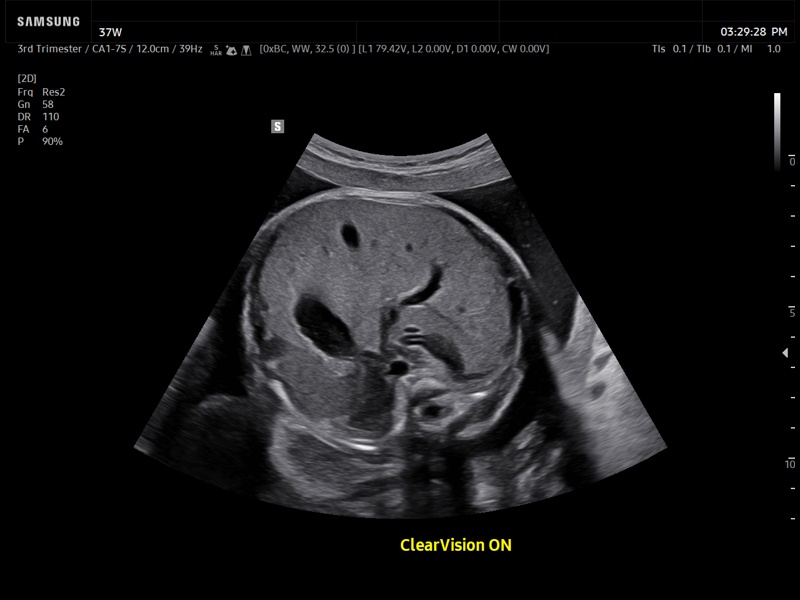

[RU] Ultrasound image №934: Fetal abdomen using the ClearVision filter. 3-rd trimester, convex probe 1-7 MHz.

Echogramm was received by ultrasound scanner Z20 (new model).